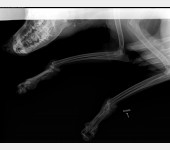

Leoś przebywał długie lata w schronisku w Raciborzu. Nikt Leosia nie chciał adoptować , taki był wycofany , bał się ludzi a w szczególności mężczyzn , co sami na sobie odczuliśmy jeżdżąc na wizyty zapoznawcze do hotelu w Gliwicach gdzie został przetransportowany. Leoś skradł nasze serca. Pomimo nie małych wątpliwości podjęliśmy decyzję o adopcji Leona i to była najlepsza decyzja. Leoś to piesek o wspaniałym charakterze , zrobił bardzo duże postępy , bez nas nigdzie się nie ruszy. Jesteśmy zmuszeni prosi o pomoc. Niestety okazało się , że nasz pupil zaczął mieć problemy z chodzeniem. Diagnoza lekarska była jednoznaczna, bez operacji Leoś przestanie chodzić. A opis lekarza ortopedy brzmiał tak : CAŁKOWITE ZWICHNIĘCIE STAWÓW NADGARSTKOWYCH , CAŁKOWITE ZERWANIE WIĄZADEŁ , DAWNE ZŁAMANIE KOŚCI PISZCZELOWEJ Z NIEPRAWIDŁOWYM ZROSTEM. LICZNE ZWYRODNIENIA STAWÓW, Załączam zdjęcia RTG .

Obecnie Leoś jest po operacji łapy przedniej lewej co ilustrują zdjęcia.